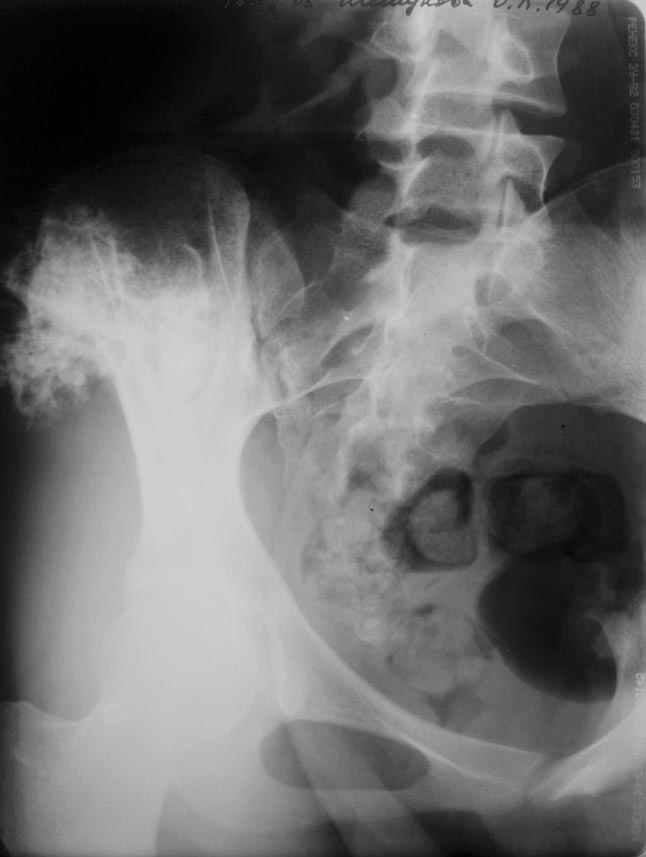

Остеохондрома подвздошной кости

еще фото